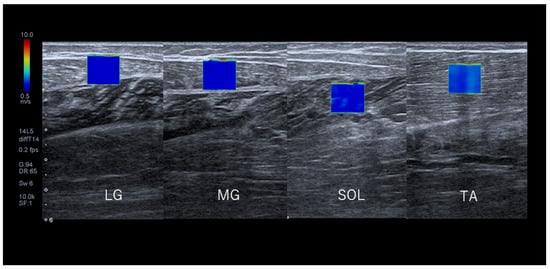

2.4. Measurement of SWV

2.6. SWV Measurements